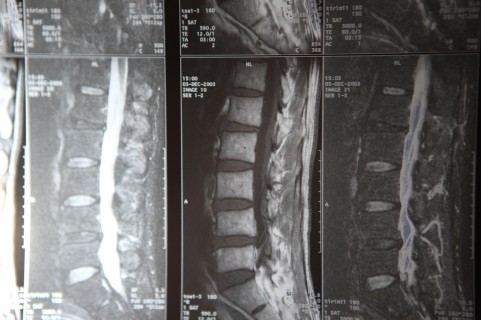

最先端医療器具、医療知識を基に

各検査で身体細部まで状態を調べます。